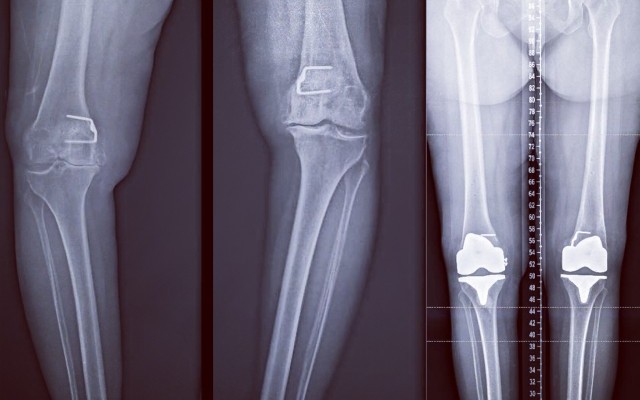

Know all things about Knee Replacement Surgery Procedure.

If you are considering a Total Knee Replacement or are having one soon, this video will help you understand what the surgeon will be doing. I should clarify that I no longer use rods inserted into the tibia and the femur as I use computer navigation. I do use bone cement to fix the implants to your bone. My patients usually stay in the hospital for 2 days and are walking the same day of the...

Total Knee Replacement vs Resurfacing

With the invent of new surgical techniques and instruments Knee Replacements can now be performed almost like Resurfacing. Taking as little bone as possible and resurfacing it with the equal amount of metal and plastic. Total Knee Replacement vs resurfacing The attached picture is from a knee arthroplasty I performed today. This is the actual picture of the bone cuts I performed on the...

It is important to understand that there are multiple bony cuts that are delicately balanced with each other so that the knee moves in a balanced fashion on both sides, and the patient does not feel insecure or unstable. I have created my own surgical technique for knee replacement that intricately predicts the ligament balance and accommodates the bony cuts to fit the ligament envelope. I...